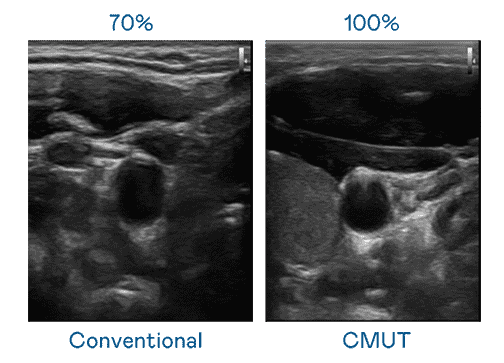

CMUT 技术是一种用电容式微机电元件来产生超音波讯号的技术。。与传统 PZT 压电式技术相比,,CMUT 频宽增加 30%,,更宽频的超音波讯号让影像解析度大幅提升,,是实现高影像品质医疗超音波扫描、、、促进精准医疗发展的关键技术。。。。

大频宽带来超清晰影像

超音波影像的解析度高低,,,首先取决于探头能发出的讯号频宽。。。糖果派对 CMUT 可提供高清晰的超音波讯号,,,提供高频宽、、、、高灵敏度、、影像纹理细节更高的超音波影像,,,,协助医护人员缩短影像判读时间及利用精准的医疗影像进行诊断。。。